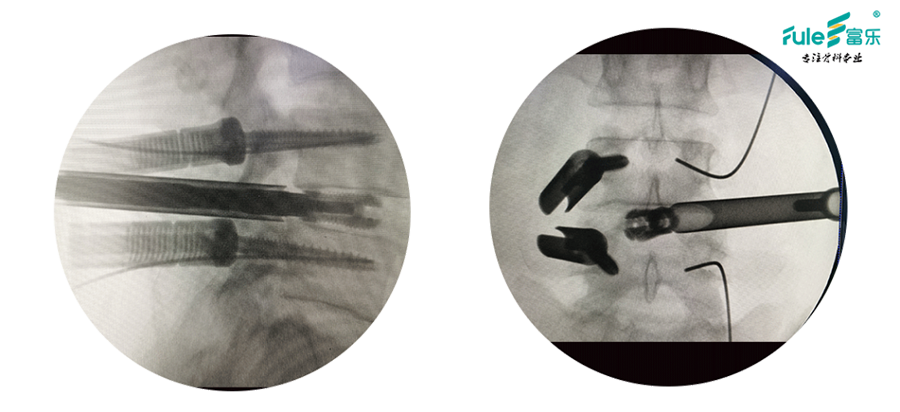

• 透视定位,建立工作通道

•  经皮钉棒固定